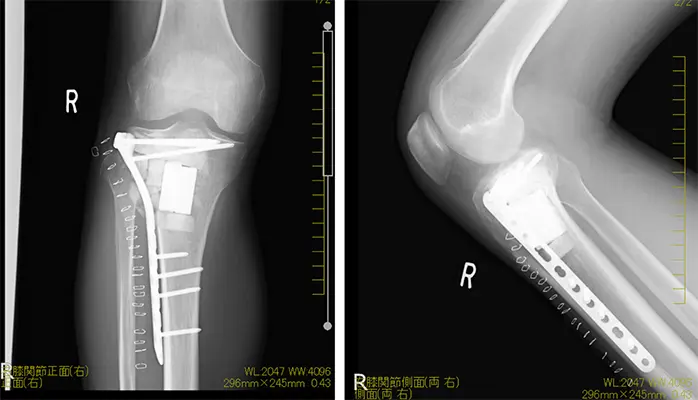

手術記録

拡大掻爬術+フェノール処置+人工骨移植+プレート固定施行.生検時の皮切を利用し,前外側皮切で展開.脛骨外側を大きく開窓した後に周囲骨髄が出るまで掻爬を施行 (Figure 4).次にエアトームを用いて拡大掻爬後に熱焼却・フェノール処置を施行(Figure 5, 6).イメージ下に十分掻爬ができたことを確認後に,気孔率の高いOSferion®顆粒を軟骨下骨に充填後,下支えをするようにOSferion®ブロックを留置.その上で同OSferion®ブロックを支えるように気孔率60のOSferion®ブロックを充填(Figure 7).次にシンセス社製外側用Locking Compression Plate (LCP)を設置(Figure 8).近位軟骨下骨にrafting screwとしてlocking screwを4本挿入,遠位にもlocking screwを4本挿入固定.骨内にアミカシン5A注入,ドレーンを留置し追層縫合,閉創し,手術終了となった.術直後に正面像および側面像を撮影し,明らかな異常認められないことを確認した(Figure 9).

単純な掻爬術の局所再発率は約50%とされ,75%は2年以内,残りの25%が5年以内に再発する.再発予防のために健常組織まで掻爬する拡大掻爬術が行われる.さらに凍結療法,フェノール処置,アルコール処置,熱焼却などの補助療法を行うことで,再発率が低下すると報告されている.GCTの悪性化は稀であり,悪性化する原因は通常は放射線被爆である(Kadowaki et al. 2012).組織学的には骨肉腫が最多だが,悪性線維性組織球腫や骨線維肉腫への悪性化も認められている(Heffernan et al. 2007).機能評価などの理由がない限りは5年以上のfollow-upは必要ないが,局所再発した患者に対しては肺転移を考慮し胸部CTによる精査が望ましい.当症例においては,術後1日目から車椅子移乗,3日目から10kg荷重歩行.術後2ヶ月で全荷重歩行となり,歩行時の疼痛も認められていない.半年以上経過した現在でも明らかな再発は認められず,人工骨も置換されており,現時点までの経過は良好である(Figure 11).